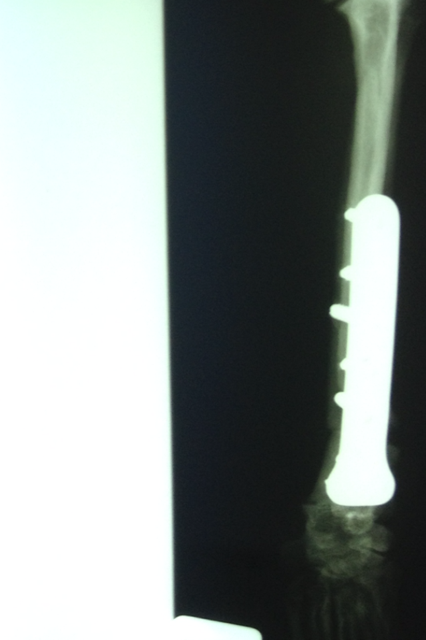

In sechs Wochen erfolgt dann die zweite OP.

Wir danken herzlich für die Geldspenden, die dies alles erst ermöglicht haben - aber bitten auch dringend um weitere Überweisungen, denn wir mussten heute auch Griffin operieren lassen, der sich mit Kniescheibenproblemen herumplagte. Und weil Lucy auch Probleme zu haben scheint, haben wir sie heute mitgenommen zum Röntgen. Es stellte sich leider heraus, dass sie einen Kreuzbandriss hat, der ebenfalls operiert werden muss.